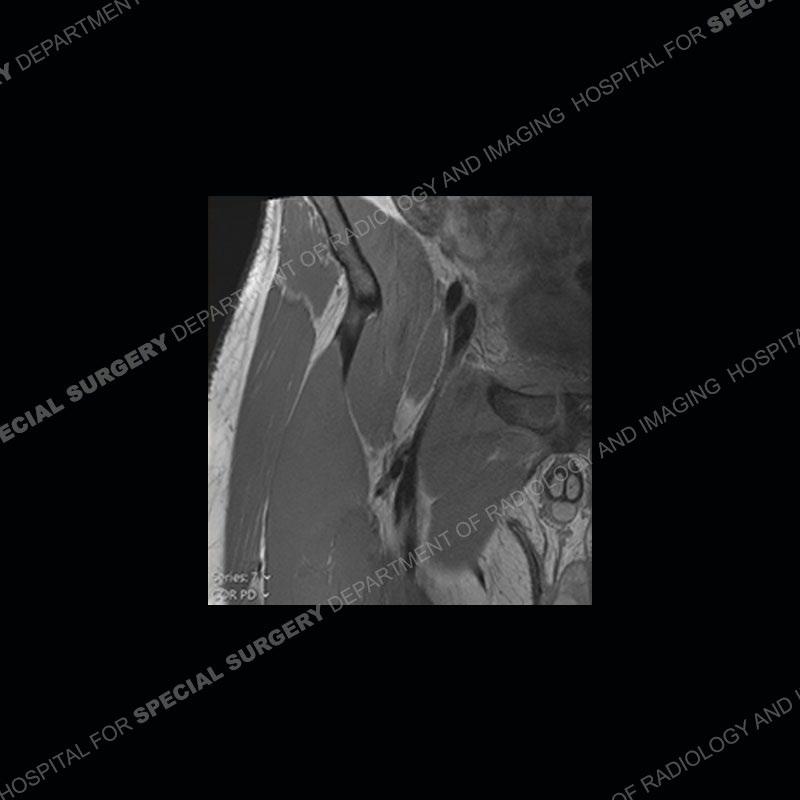

Subsequent MRI in a very short time interval shows markedly increased abnormality of the ramus and increased edema and “mass” of the soft tissue. Post contrast imaging shows multiple, rim enhancing collections of the soft tissue and similar albeit less conspicuous enhancing collection of the ramus.

The repeat MRI, with the marked degree of increased abnormality of the bone and soft tissue shifted the diagnosis to a high degree towards infection. Even the most aggressive of neoplasms would not have that the degree of change in a 3-day time span. The CT study was shown before the repeat MRI but actually occurred just after the repeat MRI. It helped confirm the destructive process of the ramus and particularly the abnormal architecture along the inferior margin. The patient went on to have a CT guided aspiration of one of the soft tissue collections with 4cc of purulent fluid obtained. A surgical irrigation and debridement of the bone and soft tissue was performed. A PICC line was placed and the patient is currently undergoing IV antibiotic treatment with a possible repeat irrigation and debridement.